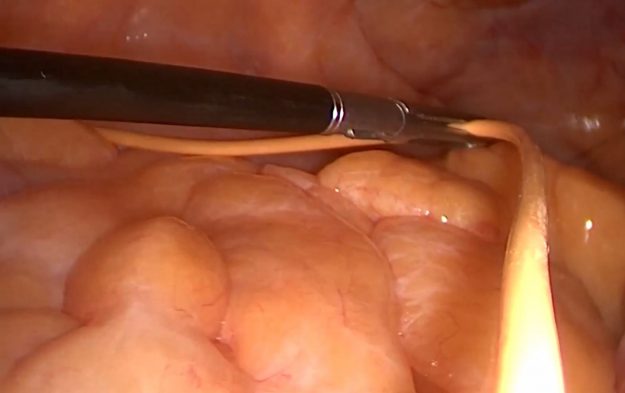

Ασθενής γυναίκα 58 ετών με πονοκεφάλους και διαταραχές όρασης. Ο οφθαλμολογικός έλεγχος έδειξε οίδημα οπτικών θηλών άμφω και σημαντικό περιορισμό των οπτικών πεδίων. Τα συμπτώματα της ασθενούς ήταν προοδευτικά επιδεινούμενα, το ίδιο και οι εξετάσεις της. Η μαγνητική εγκεφάλου ανέδειξε ευμεγέθη αραχνοειδή κύστη δεξιά κροταφικά με σημαντική πίεση επί του υγιούς εγκεφάλου και παρεκτόπιση των…